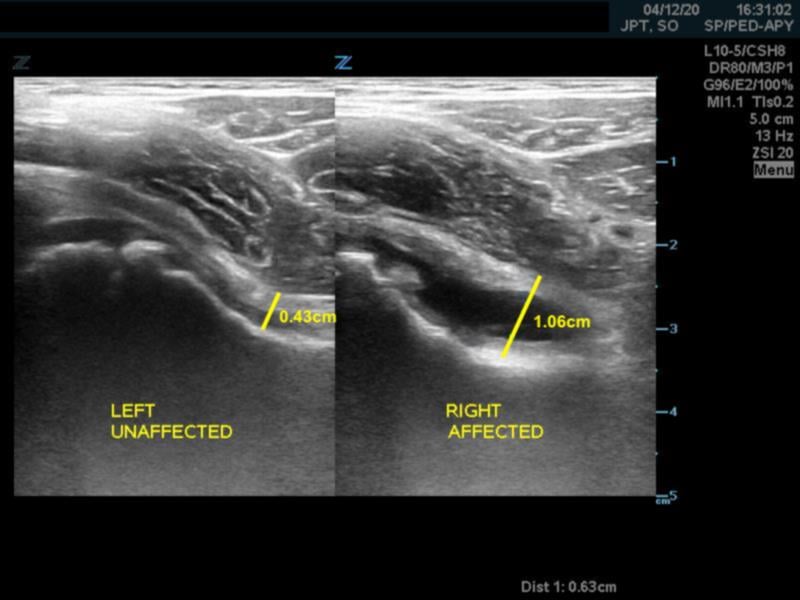

- A capsular-synovial thickness >5 mm, or >2 mm difference compared to the asymptomatic contralateral side indicates hip joint effusion in children

- Figure 4. Capsular-synovial thickness measurement >5mm in hip effusion (right)

- Joint capsule also appears convex instead of concave in case of effusion